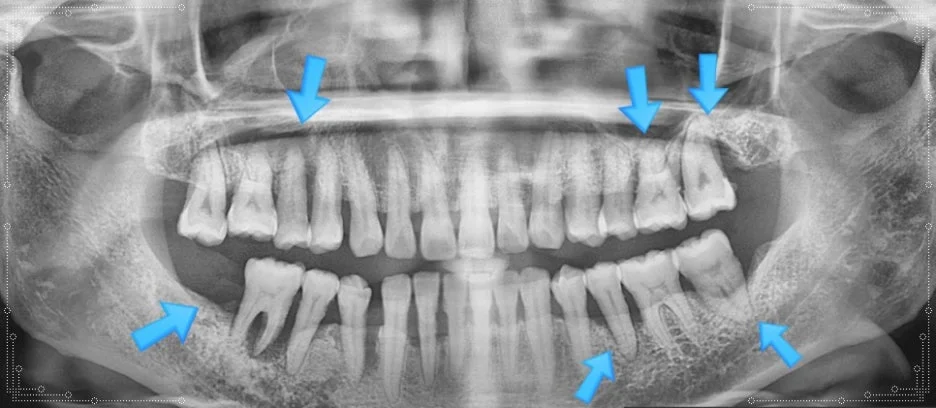

오산 치아진단 엑스레이 얼마나 꼼꼼히 하느냐가 중요합니다. 안녕하세요 서울버팀치과 엄용국원장입니다. “치과에 방문해 치료를 받았습니다.” 하지만 치과에서 치료를 받았다는 사실만으로 항상 적절한 치료가 이루어졌다고 단정하기는 어렵습니다. 정확한 진단을 위해서는 엑스레이 촬영...